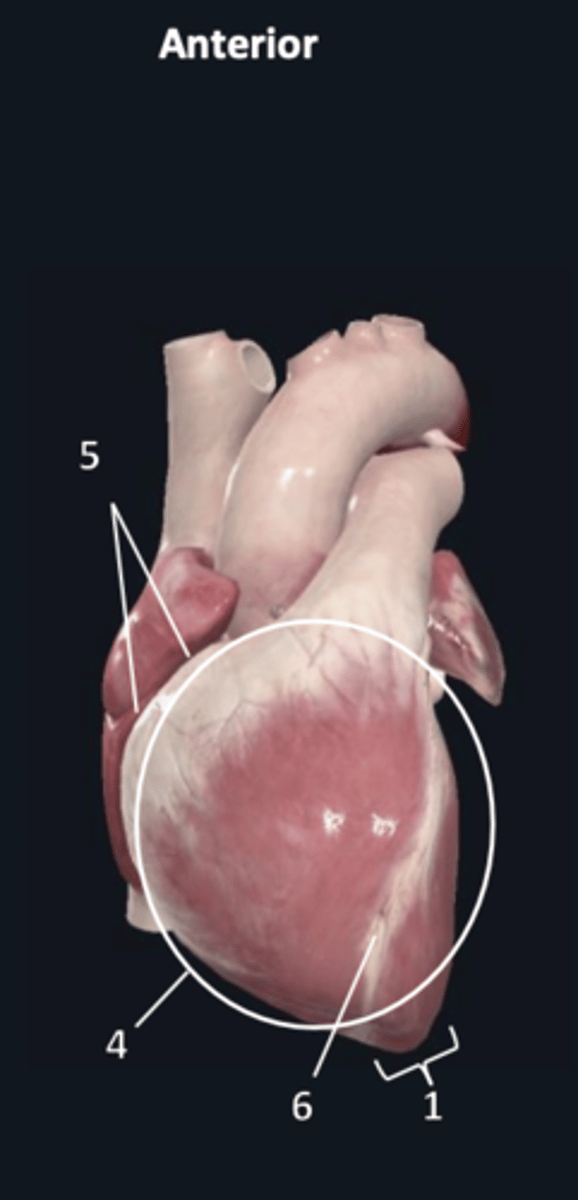

sternocostal surface

4

atrioventricular groove

5

anterior interventricular sulcus

6